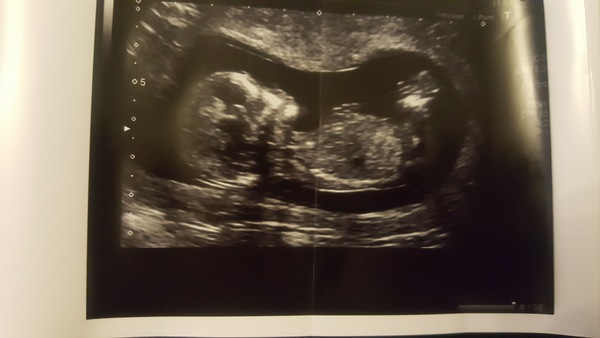

Hey all! So when my friends and relatives have been expecting I've loved using 'theories' to guess the gender and quite a lot of the time I have been right. Based on skull and nub theory. We had our scan today and baby is measuring 12 week 5 days. I really wish I had asked for a nub picture as I can't see it on this pic. I think I am swaying more team blue. What do you all think? :)

Skull nub indicates girl. Nub parallel to the spine is a girl, at angle is a boy. This one looks parallel. I have a girl and a boy and a girl on the way. My boy scan looks distinctly different but girls look very similar more like urs. one way to find out is gender scan, private will scan and tell you at 17 weeks, did with all of mine, well worth the money.

That's interesting babynelly2010 I have jut looked up pictures of nubs and now I am thinking that actually it doesn't seem to point upwards and maybe is more girly. We are going to book in for a gender scan! This is a picture of my new baby scan and my baby boy. Boy is on the bottom. I think they are quite different but then again they are laid slightly differently!

Writerwannabe83 the skull theory is based on the shape of the babies forehead. Rounder is meant to lean more towards a girl and more rectangular is for a boy.

Skull theory is not reliable at all in fetuses but nub csn be very. It's not just based on the angle of the initial white line for a boy, you also have to look out for stacking which sits on top of the nub, this is what gives the nub an angle even when it appears relatively parallel. Yours makes me think boy because it is not as long and thin as a girls nub and I also think I can make out stacking.